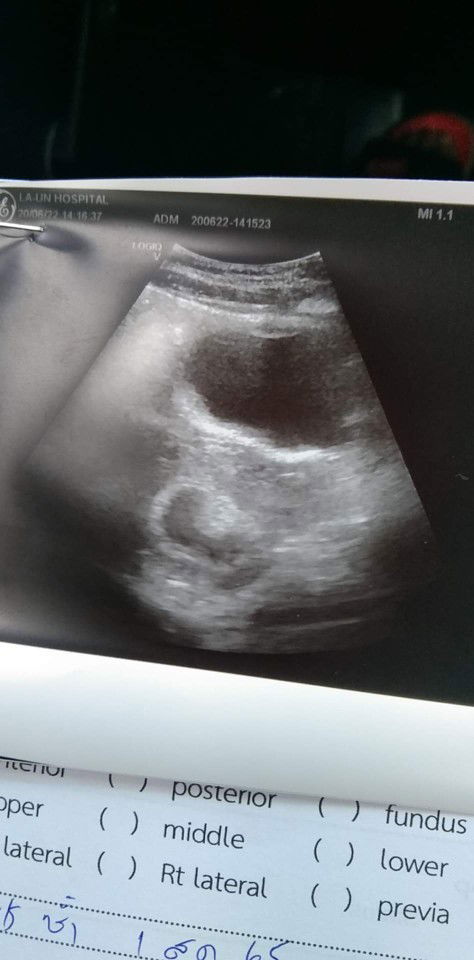

ไม่เจอตัวอ่อน😔🥲

6วีคแล้ว อัตซาวมาไม่เจอตัวอ่อนเลยค่ะ แม่บ้านไหนเป็นแบบนี้บ้างค่ะ 😔😔

แม่ๆบ้านไหนอัตซาวด์แล้วเจอเจ้าจิ๊วบ้างค่ะ กี่วีคถึงจะเห็น แม่บ้านนี้6วีค ยังไม่เจอเลยค่ะแม่เครียดมาก